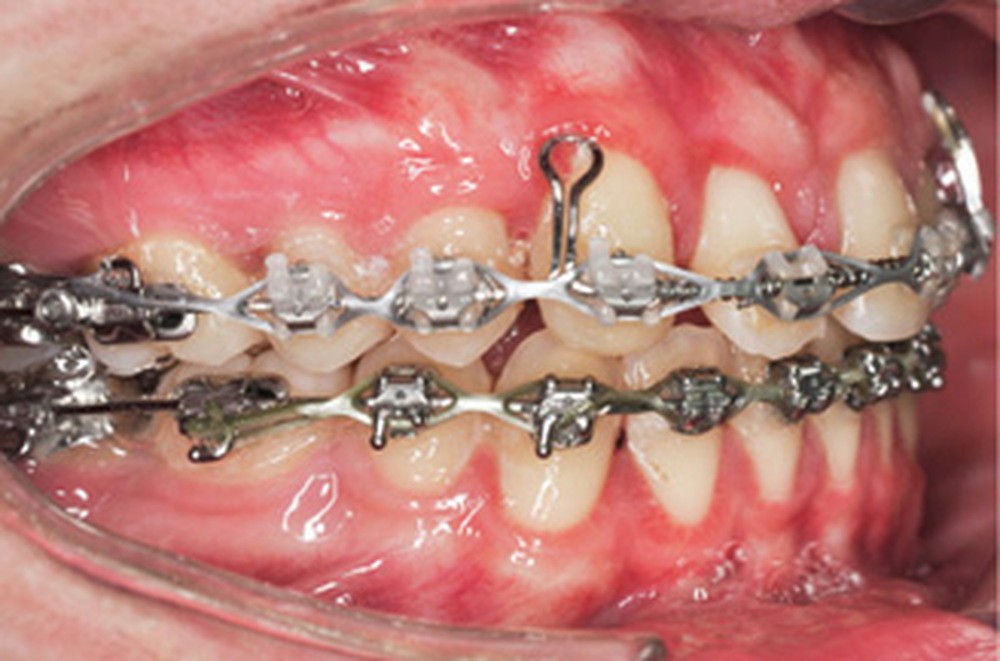

Le nivellement a nécessité trois arcs en Copper-NiTi (.014/.016 x .022/.019 x .025). Les mécaniques intra arcades (fermeture des espaces) et interarcades (élastiques de tractions intermaxillaires de classe II) ont été effectuées sur des arcs en acier .019 x .025. La gestion asymétrique de la mécanique de rétraction maxillaire a débuté par le recul de 23 (ancrage postérieur dentaire + élastiques intermaxillaires de classe II). Une fois 23 symétrisée avec 14 (substituant la 13), le centrage de 12 a débuté pour le remplacement de la 11. La rétraction du groupe antérieur par un arc à boucles de rétraction en acier .019 x .025 permet d’ajuster le torque radiculo-palatin pour contrer le rabbiting antérieur (fig. 2a-c).